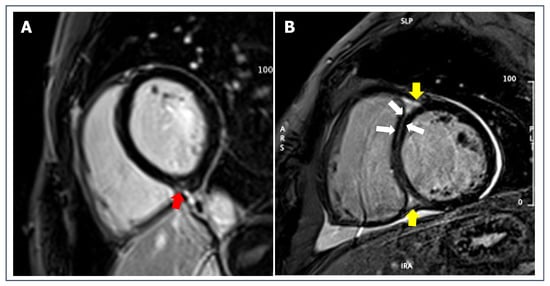

5.4. Non-Ischemic Scar

5.5. Left Ventricular Non-Compaction